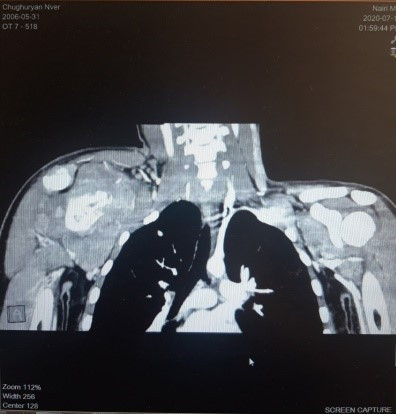

Рисунок 1. Радиологическое изображение лопатки